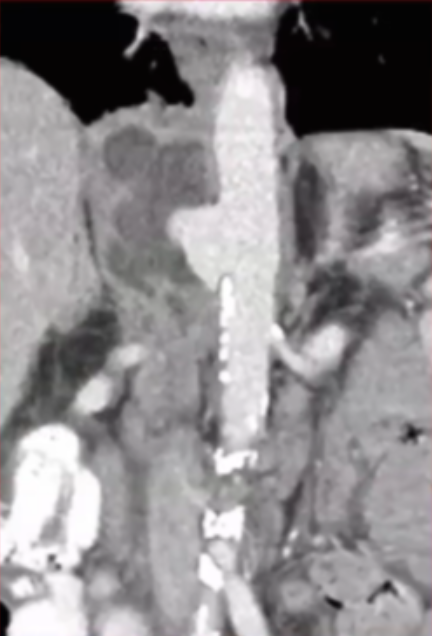

该研究(2005年9月-2024年5月)共纳入175例感染性主动脉瘤患者(男性142,女性33例),平均年龄64.8岁。这些患者患病部位为胸主动脉31例、内脏分支受累26例、胸腹联合5例、腹主动脉113例。

临床表现主动脉周围炎症97%、瘤体渗漏76%,部分患者合并椎体侵蚀、腔静脉血栓。

案例3:75岁男性沙门氏菌感染导致的感染性主动脉弓瘤,采用“颈动脉-颈动脉搭桥、颈动脉-左锁骨下动脉搭桥+TEVAR(胸主动脉腔内修复术)+无名动脉烟囱技术”的治疗方案。术前及术后至6年半的随访结果显示,动脉瘤得到有效控制,患者长期预后良好。

案例4:45岁女性,胸、腹主动脉同时感染,术前与术后9.5年影像对比可见,经过治疗动脉瘤情况得到显著改善,长期随访显示治疗效果稳定,瘤体得到有效控制。